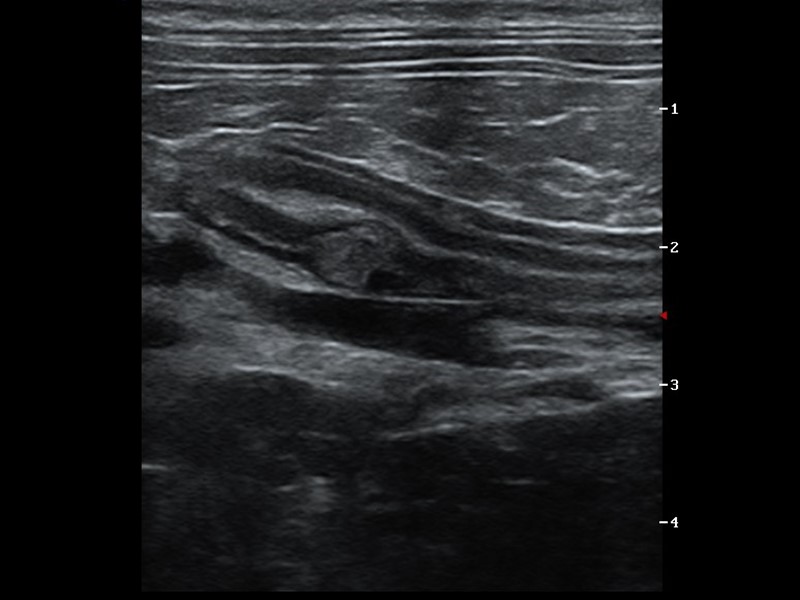

Intermediate abdomen, taking the next step

This course is applicable to those who have had some training in abdominal ultrasound or are already performing basic abdominal ultrasound. Develop your skills further into a systematic technique, ensure you are not making the common mistakes and build your confidence with the trickier organs.

- ultrasound technique to include longitudinal and transverse images of all main abdominal organ